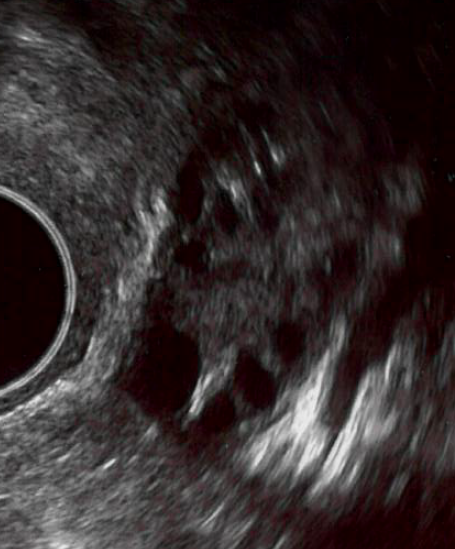

Om de kans op zwangerschap te vergroten, krijgt u medicijnen voorgeschreven die de eierstokken stimuleren. Op die manier komen meestal twee eiblaasjes tot ontwikkeling in plaats van 1 (zoals in de natuurlijke cyclus). Nadat u zich op de eerste dag van de menstruatie heeft aangemeld, heeft u een afspraak gekregen voor een uitgangsecho op de tweede of derde dag van de cyclus. Deze afspraken vinden plaats op het IVF-centrum. Bij een uitgangsecho wordt gekeken of er geen cystes of andere afwijkingen aan de baarmoeder of eierstokken worden gezien die de behandeling kunnen belemmeren. Het is mogelijk dat u wordt gevraagd om bloed te laten afnemen. Hierbij kunnen verscheidene hormonen worden bepaald. Dat kan (indien nodig direct) in het IVF-centrum. Meestal worden er geen bijzonderheden ontdekt en kan de behandeling doorgaan.

Op basis van leeftijd en het beeld van uw eierstokken bij de uitgangsecho bepalen wij de startdosering. De standaard dosering is 75IE Menopur®. Het kan echter zo zijn dat uw eierstokken niet zo reageren zoals dat we van te voren hadden verwacht. Dit kan betekenen dat door de stimulerende medicijnen meer ei-blaasjes tot ontwikkeling zijn komen dan gewenst. Er is dan sprake van overstimulatie. Hoe meer ei-blaasjes, hoe groter de kans op een meerlingzwangerschap. Een meerlingzwangerschap zien wij als een complicatie omdat er bij een meerlingzwangerschap meer risico’s zijn voor zowel u als de ongeboren kindjes dan bij een eenlingzwangerschap. De behandeling wordt daarom afgebroken als er meer dan drie ei-blaasjes zijn met een doorsnede van 14 mm of groter.

Voor de start van de behandeling zal er met een uitgangsecho gekeken worden of er cystes (restjes van de ei-blaasjes gevuld met vocht) aanwezig zijn. Dit komt vaker voor als een vorige behandeling is gestaakt in verband met overstimulatie, maar kan ook na een natuurlijke cyclus of goed verlopen IUI behandeling plaatsvinden. Dit is niet schadelijk, maar kan een nieuwe behandeling wel verstoren. U krijgt het advies een maand rust te nemen of één strip van de anticonceptiepil te slikken.